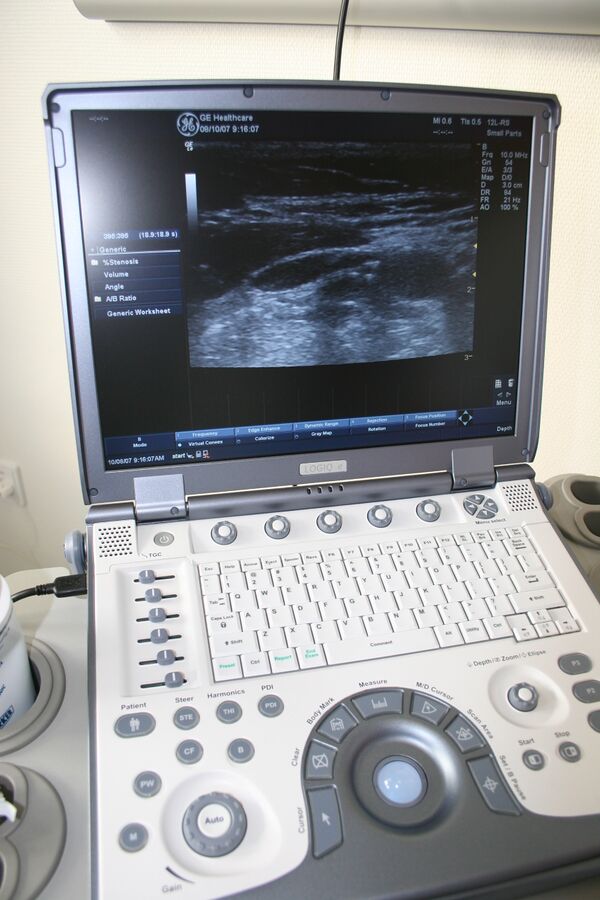

Аппарат ультразвуковой диагностики

Аппарат ультразвуковой диагностики (УЗ-сканер) — прибор, предназначенный для получения информации о расположении, форме, размере, структуре, кровоснабжении органов и тканей человека и животных[2][4][5].

По форм-фактору УЗ-сканеры можно разделить на стационарные и портативные (переносные)[4][5], к середине 2010-х годов получили распространение мобильные УЗ-сканеры на основе смартфонов и планшетов.